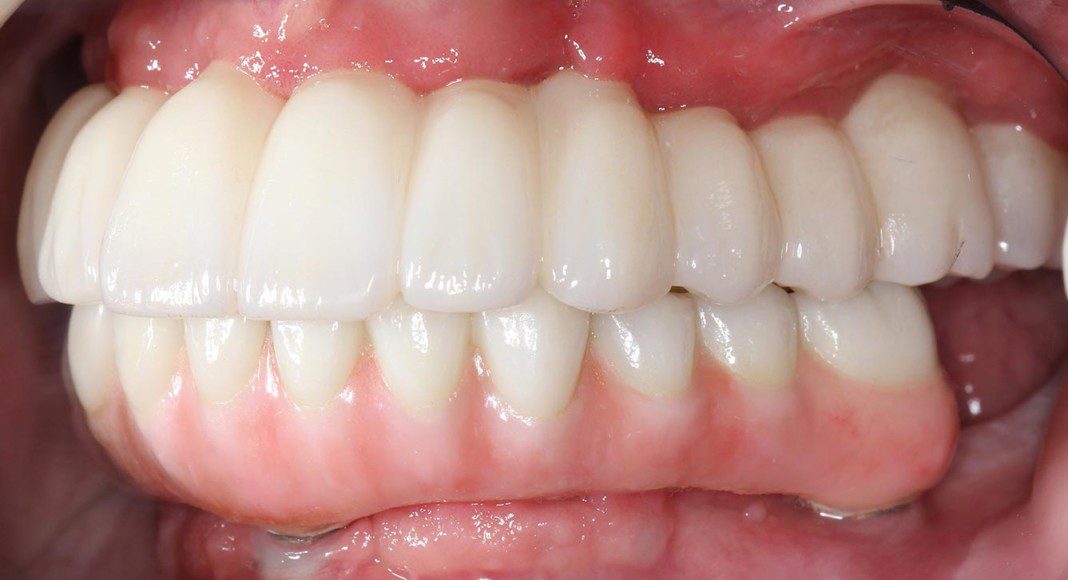

Stage one: Fixed, plastic temporaries in both arches. Aesthetic improvements are already quite obvious. These will serve the patient for several weeks and prepare him for the first surgery.

At the first surgery, strategic teeth are removed and some implants placed. The temporary bridges are modified to accommodate the new arrangement.